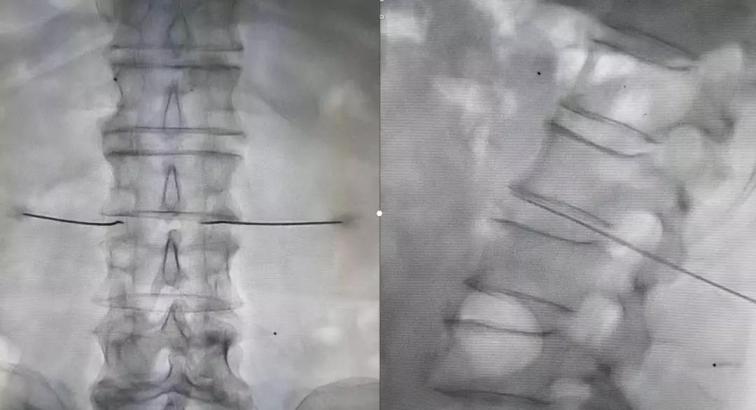

隨后制定了詳細(xì)的診療方案:1、進(jìn)一步完善相關(guān)檢查;2、每天早上給予骶管封閉、三氧血治療;3、實(shí)施腰交感神經(jīng)阻滯改善下肢血液循環(huán);4、待患者對(duì)初步治療效果認(rèn)可滿意后,給予腰交感神經(jīng)損毀治療,以此改善下肢血管痙攣性疼痛以及下肢血液供給狀況,給予保肢,達(dá)到治愈的目的。

診療方案雖然有了,但是要?jiǎng)褡杷伟⒁毯图覍佟敖刂钡哪铑^還真是頗費(fèi)周折。李巍安慰家人,按照醫(yī)生的方法治療3天,如果效果不好,我們?cè)偕塘拷刂氖虑椤<胰税胄虐胍傻拇饝?yīng)了。8月20日,經(jīng)過(guò)幾天的初步治療,宋阿姨和家人們明顯感覺到了患病小腿上的好轉(zhuǎn)變化。李巍又詳細(xì)向患者及家屬解釋了交感神經(jīng)阻滯及損毀能夠給疾病帶來(lái)的相關(guān)改善,并在征求病人及家屬同意后,給予患者腰交感神經(jīng)損毀治療。實(shí)施治療的第二天,宋阿姨下肢血管神經(jīng)性疼痛癥狀明顯緩解,下肢供血明顯改善,左下肢皮膚溫度較術(shù)前明顯提升,結(jié)痂周圍皮膚顏色也變得紅潤(rùn)。